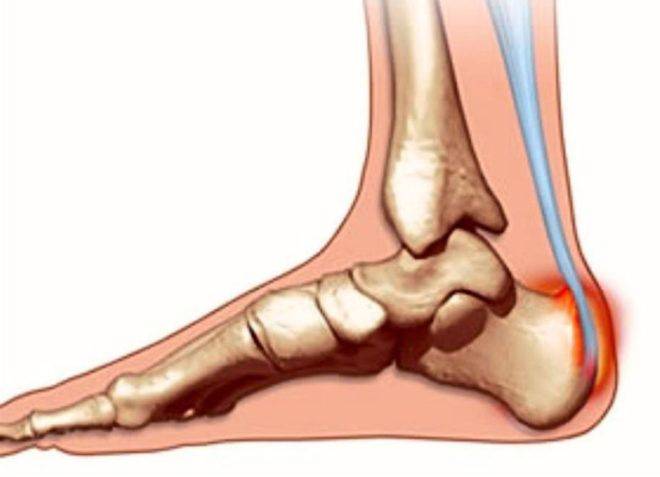

Этиология и течение

Артроз пяточной кости — это болезнь, которая имеет хроническое течение. Недуг поражает хрящевые ткани соединения и провоцирует развитие воспаления вокруг сустава. Со временем артроз деформирует суставные части костей, активизирует патологические процессы вокруг соединения. Главной причиной развития болезни считают неправильный обмен веществ в клетках, который впоследствии приводит к разрушению хрящевой ткани. С развитием артроза хрящ теряет свою эластичность, становится сухим и соответственно в соединении ограничивается двигательная активность. В процессе прогрессирования заболевания патологические процессы интегрируют на другие суставные части. Возникновение артроза могут спровоцировать следующие причины:

При артрозе образовываются костяные наросты — остеофиты. Без должной терапии этот процесс приведет к полной неподвижности сустава.